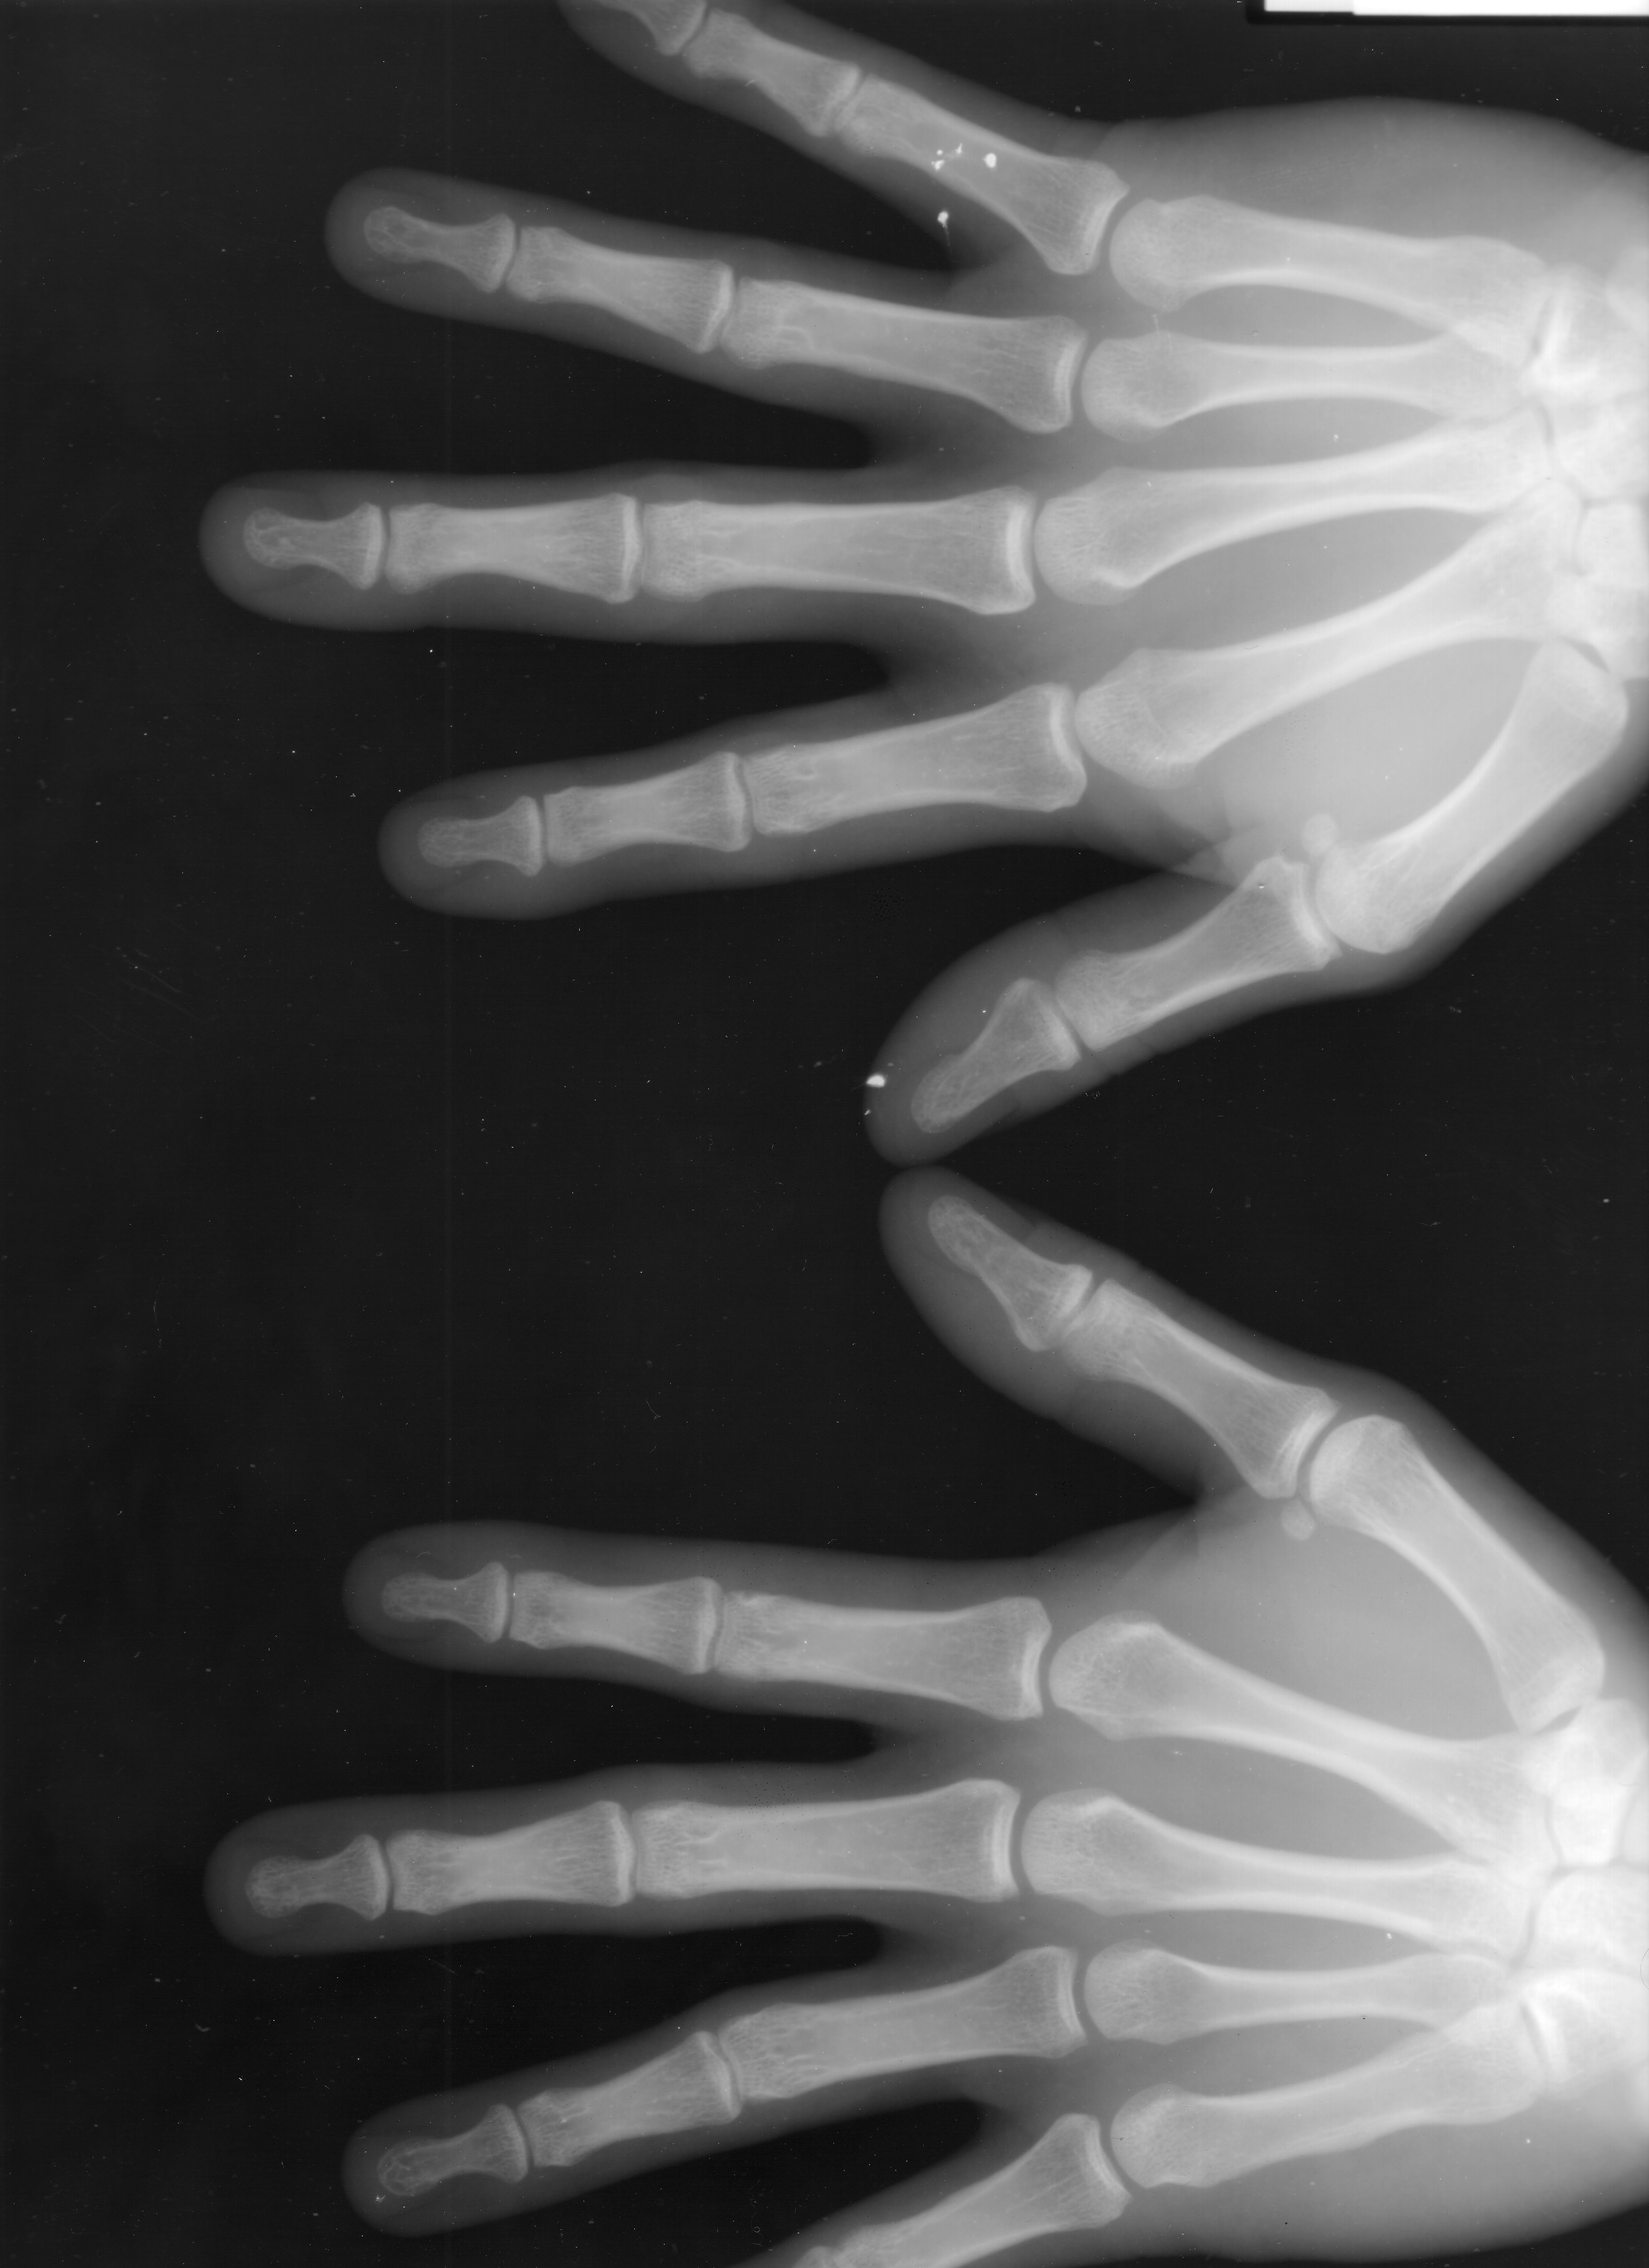

Hands

Taken at 75KV 40mAS, posterioanterior view